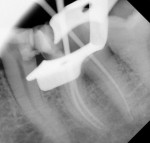

Shaping of canals was done using a nickel titanium file (HyFlex™ CM, Coltene, coltene.com), and cleaning was done with the aid of 5.25% sodium hypochlorite and normal saline. Canals were enlarged up to 25/0.04 in the mesial canals (mesiobuccal and mesiolingual) and 30/0.04 in the single distal canal. A small piece of a synthetic collagen material (CollaTape®, Zimmer Biomet Dental, zimmerbiometdental.com) was gently compacted to produce a barrier at the level of furcation. Gray MTA (MTA Angelus® [Gray], Angelus, angelusdental.com) was mixed according to the manufacturer's instructions and seated on the CollaTape barrier. Gutta percha points were placed in the canals to avoid the flow of MTA into the canals (Figure 4).

A moist cotton pellet was applied over the MTA to promote the setting of the material, and the access cavity was sealed with temporary filling material (Cavit™, 3M Oral Care, 3m.com). The placement of the MTA was confirmed radiographically (Figure 5).